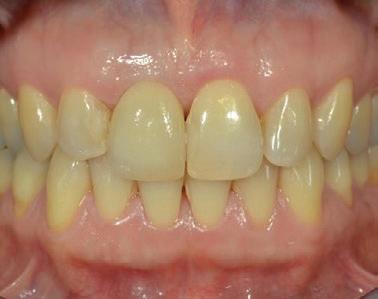

Cette formation de deux jours a pour objectif de vous permettre de diagnostiquer, planifier et réaliser des restaurations implantaires, tant unitaires qu’en édentation partielle fixe impliquant deux implants ou plus. Le contenu aborde les fondements essentiels de la restauration sur implant, ainsi que des notions plus avancées en implantologie prothétique.

Vous verrez l’ensemble des étapes cliniques — de la planification au suivi post-insertion — dans le but d’obtenir des restaurations fonctionnelles, esthétiques et durables. Vous aurez également l’opportunité d’observer des cas cliniques en direct, tant chirurgicaux que prothétiques, réalisés sur des patients, depuis la salle de cours ou la salle de traitement grâce à une retransmission vidéo en temps réel.

Temporisation en région antérieure

Gestion du complexe mucco-gingival et pontique ovoïde

Modification du profil d’émergence pour un contour gingival optimal